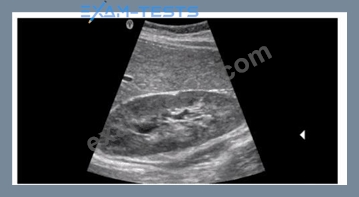

Question 99

Which transducer was most likely used to create this image?

A ultrasound of a fetus Description automatically generated